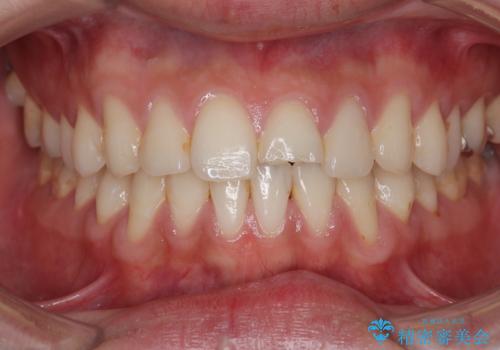

前歯の根のところに違和感がある|根尖性歯周炎|精密根管治療|オールセラミッククラウン|見た目も改善